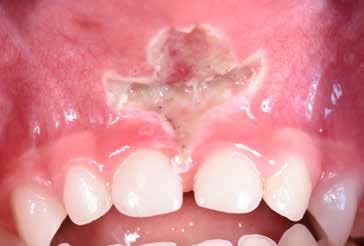

Frenuli delle Labbra

Nell’età della dentizione mista, di tutti i frenuli risulta importante soprattutto quello del labbro superiore (vedi capitolo 10). Il forte sviluppo di tale frenulo può causare la formazione di un distema mediale (Olivi et al. 2010). Per quanto concerne la diagnosi differenziale, la frenulectomia risulta indicata soltanto qualora il frenulo labiale presenti un’inserzione molto bassa e si fonda, sul lato palatale, con la papilla incisiva. Sotto il proflo radiologico, tra le radici degli incisivi superiori si osserva un’incisura che indica il passaggio interosseo delle fbre. La frenulectomia dovrebbe comunque venire effettuata solamente dopo l’eruzione degli incisivi laterali superiori Figg. 17-18

S.V. Paziente di tre anni di sesso maschile, in III Classe scheletrica lieve, con open-bite, deglutizione atipica, contrazione dell’arcata superiore, tendenza alla III Classe. Alla prima visita il paziente presentava un evidente frenulo vestibolare corto, a tetto labiale che, trazionando il labbro superiore, tendeva a ischemizzarsi insieme alla papilla retroincisiva.

In situazioni simili si potrebbe anche attendere ma, poiché si rendeva necessaria una terapia ortodontica, si è proceduto ad eseguire una frenulectomia e il giorno stesso è stato consegnato al paziente l’apparecchio elastodontico per la correzione della malocclusione. Lo scudo vestibolare dell’apparecchio ha contribuito alla guarigione del frenulo stesso determinando una trazione continua sul labbro superiore.

La sequenza terapeutica ha previsto i seguenti step:

• frenulectomia laser;

• terapia elastodontica al fine di ripristinare la corretta crescita scheletrica e dentale.

Fig. 4

Fig. 8 > Dettaglio del frenulo labiale superiore corto.

Figg. 9-11 > Intervento di frenulectomia con laser a diodo.

Figg. 12, 13 > Controllo dopo ventiquattro ore.